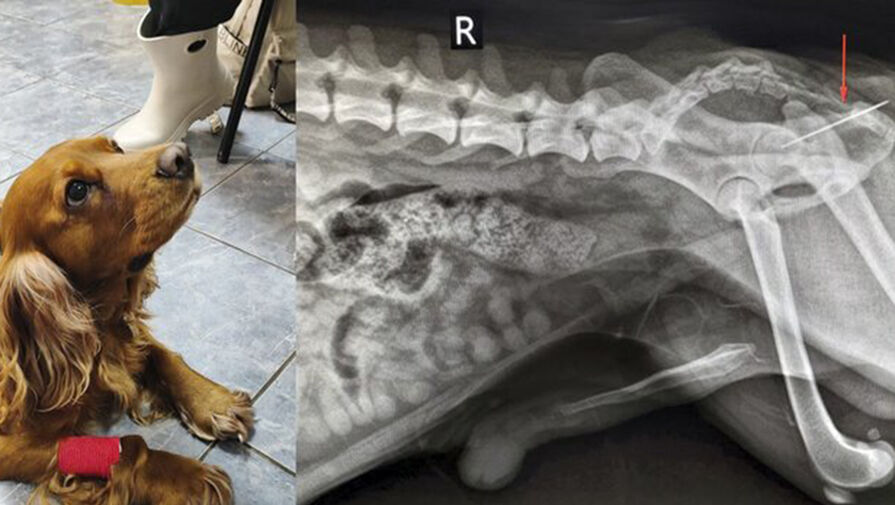

В ветклинике Коптево специалисты спасли собаку породы кокер-спаниель по кличке Вольт, которая проглотила швейную иглу. Об этом »Москве 24» рассказали в столичной госветслужбе.

«При осмотре терапевт Анна Кубатина заметила, что из заднего прохода Вольта торчит швейная нитка. Пациента срочно отправили на рентген», – добавили в пресс-службе.

Врачи установили, что за ниткой тянулась и игла, которая застряла в прямой кишке. Хирург Евгений Бахтин и анестезиолог Светлана Дорожкина провели операцию по извлечению иглы, после этого питомца отпустили домой.